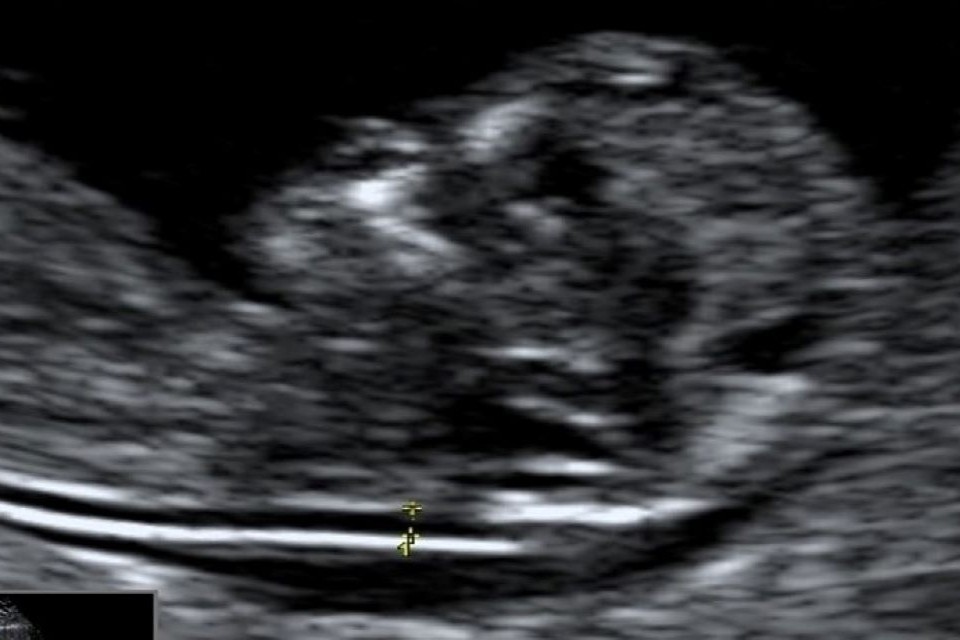

Example 1 shows 2 ultrasound images of a CRL and an NT that meet all the criteria. There is also a screenshot of what the accompanying image review tool would look like for both images.

Example 1